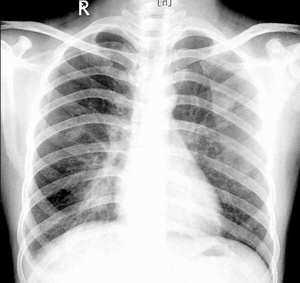

何杰金氏淋巴瘤CT圖HD的國際臨床分期(AnnArbor會議,1971)標準如下。